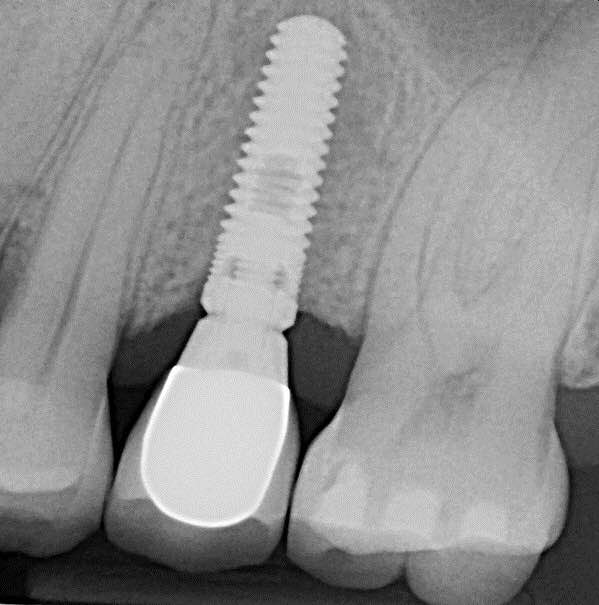

IMPLANTES Y PROTESIS

Los implantes dentales son unas raíces artificiales creados para sustituir dientes perdidos, capaces de integrarse, hasta el punto de convivir de forma sana y totalmente natural con los tejidos de la boca. Actualmente están fabricados preferentemente de titanio químicamente puro y actúan como sustitutos de las raíces dentales. Tras su colocación dentro del maxilar o de la mandíbula, sirven para que una vez están oseointegrados, apoyen los nuevos dientes artificiales que van unidos a ellos, ya sea en forma de coronas o de prótesis. Los implantes de carga inmediata es la técnica que permite colocar la prótesis, ya sea unitaria o completa, en un solo día. El uso de implantes dentales de carga inmediata se ha convertido en todo un referente en tratamientos dentales para la recuperación de piezas perdidas, facilitando que recuperes no sólo tu salud bucal, sinó, tu increíble sonrisa!